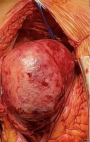

Diagnostic assessment: transthoracic echocardiography revealed a large apical pseudoaneurysm (6.6 × 8.1 cm) and a 1.2 cm post-infarction ventricular septal defect (PI-VSD) with predominantly left-to-right shunting. Left ventricular ejection fraction (LVEF) was 26%, with pulmonary hypertension (rSPAP 76 mmHg) (Figure 1). Cardiac computed tomography angiography (CCTA) confirmed a 7.1 × 8.1 cm pseudoaneurysm communicating with both ventricles, chamber dilation, RV hypertrophy, and moderate pericardial effusion (Figure 2). Follow-up coronary angiography and ventriculography showed persistent proximal and mid-LAD stenosis (85-90%), 40% mid-distal Cx stenosis (TIMI III), and unobstructed RCA (TIMI III). Left ventriculography revealed a pseudoaneurysm measuring 92 × 73 × 81 mm with hypokinesia of the anterior, anteroseptal, and lateral walls; EDV 221 mL, ESV 79 mL, EF 65%. Electrocardiography demonstrated sinus rhythm, HR 83 bpm, pathological Q waves in V1-V6, flattened T waves in I, II, III, aVL, aVF, and persistent ST-segment elevation in V2-V5, consistent with prior anterior MI. High-sensitivity troponin T was 25.3 ng/mL. Laboratory assessment revealed elevated cardiac troponin, systemic inflammation (increased CRP levels), mild hepatic enzyme elevation, moderate renal impairment (CKD C3a), and subclinical hyperthyroxinemia.

Figure 2: cardiac computed tomography angiography (CCTA); A) 3D reconstruction, where pseudoaneurism is shown with an arrow, and B) four-chamber long-axis view - showing apical pseudoaneurysm (violet) connected to the left ventricle cavity (red) and to the right Ventricle (blue); dilated chambers and serous pericardial effusion are also seen